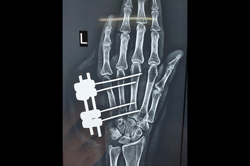

Finger Tip Injury - JESS

Metacarpal Fracture – External Fixator JESS